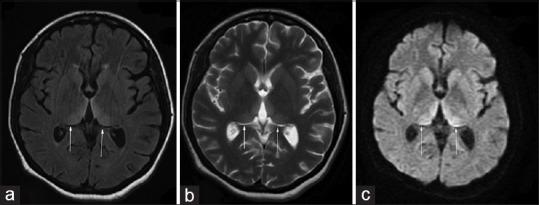

Hyperemesis gravidarum-induced Wernicke's encephalopathy (WE) is an underestimated condition. The purpose of this study is to improve its awareness and early diagnosis. We report five cases of WE secondary to hyperemesis gravidarum. Classic triad of encephalopathy, ataxia, and ocular signs was seen in four out of five patients. Two unusual features noted in this series were papilledema in one patient and severe sensory-motor peripheral neuropathy in one patient. Magnetic resonance imaging (MRI) was abnormal in all the five patients, and high signal in medial thalamus and surrounding the aqueduct was the most common abnormality (5/5). Involvement of caudate nucleus was seen in two patients with severe psychosis, and two patients had bilateral cerebellar peduncle involvement. Median time delay between onset of neurological symptoms and diagnosis was 7 days. All patients improved with thiamine, but minor sequelae were seen in four patients at 12 months follow-up. One patient had a fetal demise. Hyperemesis gravidarum-induced WE is a common cause of maternal morbidity. Typical MRI findings of symmetric medial thalamic and periaqueductal signal changes may permit a specific diagnosis. A delay in diagnosis, therefore treatment, leads to worse prognosis.

妊娠剧吐所致韦尼克脑病(WE)是一种被低估的疾病。本研究的目的是提高对其的认识并实现早期诊断。我们报告了5例继发于妊娠剧吐的韦尼克脑病病例。五分之四的患者出现了脑病、共济失调和眼部体征的典型三联征。本系列中注意到的两个不寻常特征是1例患者出现视乳头水肿,1例患者出现严重的感觉运动性周围神经病。所有5例患者的磁共振成像(MRI)均异常,内侧丘脑和导水管周围高信号是最常见的异常表现(5/5)。2例严重精神病患者出现尾状核受累,2例患者双侧小脑脚受累。神经症状出现至诊断的中位时间延迟为7天。所有患者经硫胺素治疗后均有改善,但在12个月的随访中,4例患者出现轻微后遗症。1例患者发生胎儿死亡。妊娠剧吐所致韦尼克脑病是孕产妇发病的常见原因。对称的内侧丘脑和导水管周围信号改变的典型MRI表现可能有助于做出明确诊断。诊断延迟进而导致治疗延迟会导致预后更差。